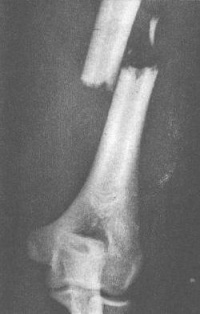

肱骨干骨折

肱骨外科颈远端1cm以下至肱骨髁部上方2cm以上为肱骨干肱骨干骨折多见于青壮年,好发于中部,其次为下部,上部最少。中下1/3骨折易合并桡神经损伤,下1/3骨折易发生骨不连。

直接暴力打击可造成横断骨折或粉碎骨折,间接暴力所致者多为斜形、螺旋形或蝶形骨折。肱骨干不同部位有不同的肌肉附着,骨折错位的方向也有不同。肱骨上段的骨折,近折端受胸大肌和背阔肌的牵拉向前内侧错位,远折端受三角肌的牵拉向上、外错位;肱骨中段骨折则相反,近折端受三角肌和喙肱肌的牵拉向外、前方移位,远折端受肱二头肌、肱三头肌的收缩向上移位,造成骨折端重叠错位。